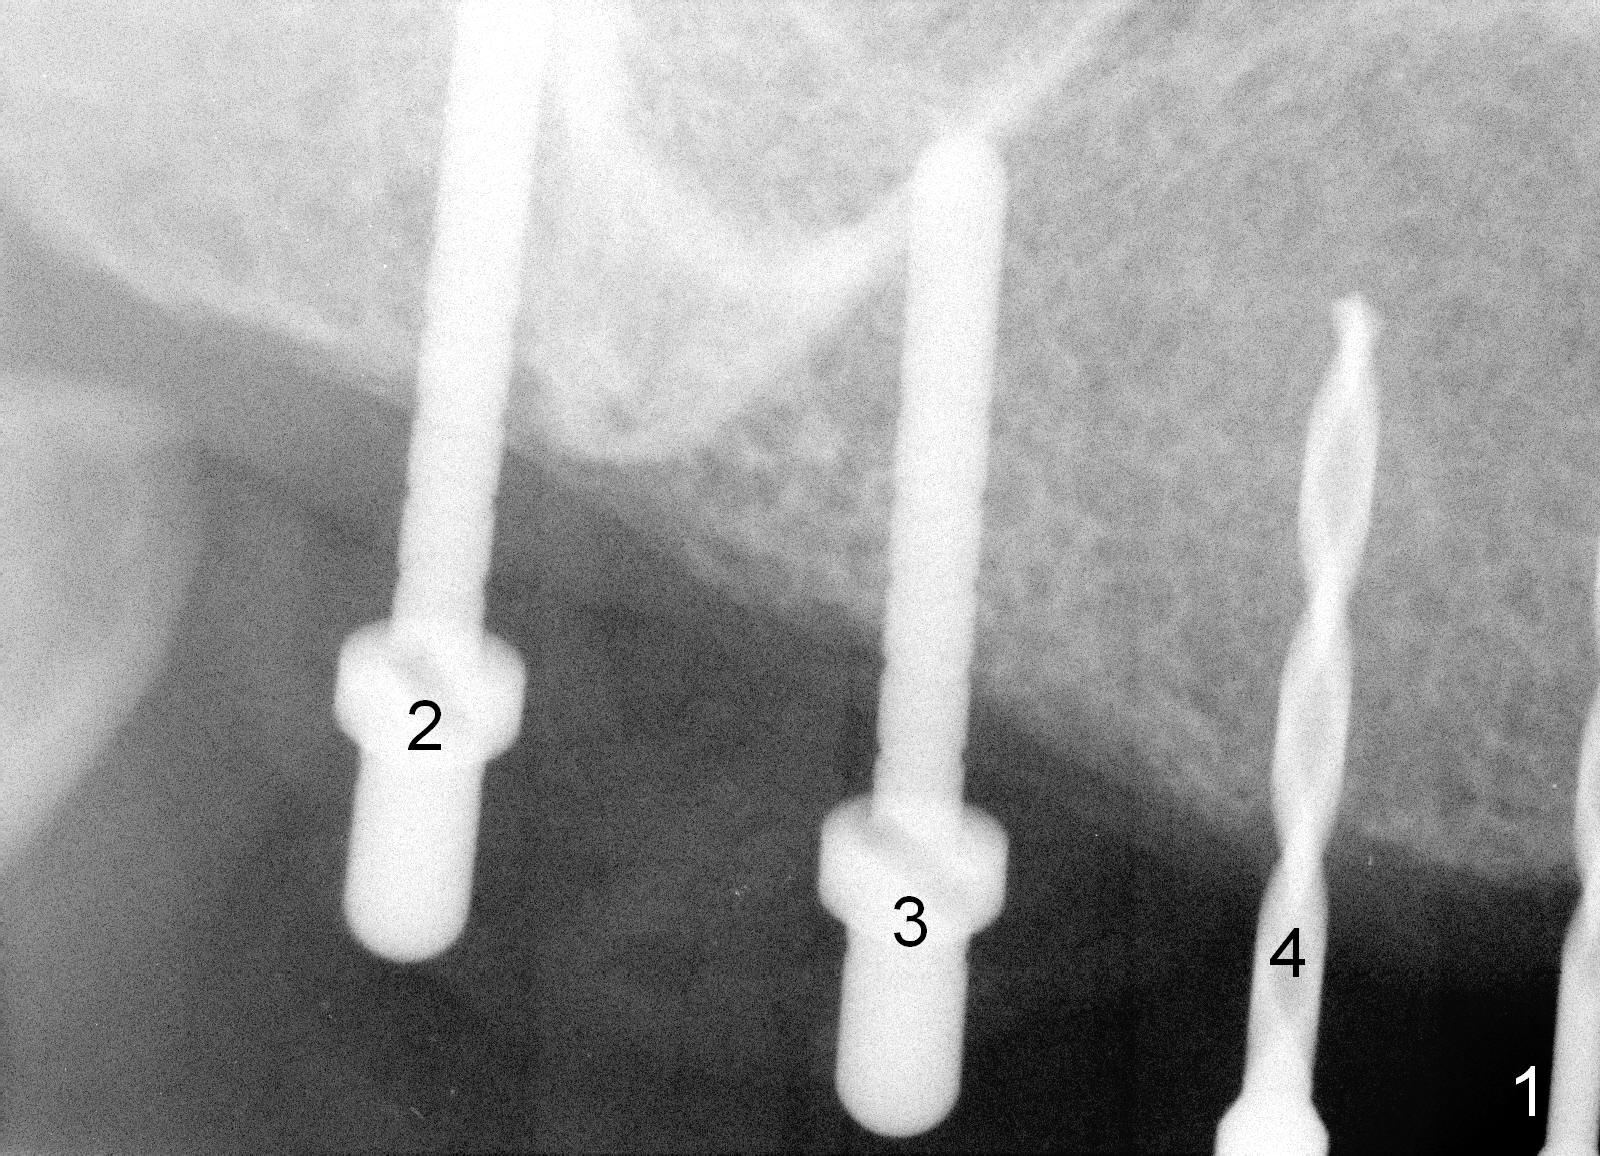

Osteotomy in the upper posteriors starts through a surgical stent for 12 mm.  After incision, each osteotomy is examined, adjusted and extended 2 mm shy of intended (Fig.1,2).  It appears that the trajectories at #4,5 are off (Fig.2).  After re-adjustment, the trajectories are acceptable (Fig.3 (red dashed line; part of the root of the tooth #6)).  Four implants are placed basically in accordance with the plan: 5.9x10 mm at #2, 5x14 at 3, and 3x14 mm 1-piece at 4 and 5 (Fig.4,5).  Fig.6 shows the narrow ridge at #4 and 5 after implant placement.  Although abutments are placed at #2 and 3, an immediate provisional bridge cannot be fabricated because of lack of enough clearance (supraeruption of the opposing dentition).